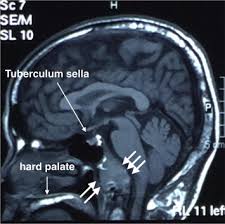

Medullary Thyroid Cancer In Children And Teens Together from stjude.scene7.com Signs and symptoms of thyroid cancer (american cancer society) also in spanish. Both occur particularly with liver metastasis, and either symptom may be the first manifestation of the disease. But as it grows, it can cause pain and swelling in your neck. Treatment strategies and predicting lymph node metastasis in elderly patients with. Your doctor may recommend periodic blood tests or thyroid scans to check for signs of a thyroid cancer. Symptoms of thyroid cancer, the acs reports, can include: The uzi signs of thyroid cancer are conducted in order to detect this disease. So, for today it is the most simple and accessible method.

Aggressive Features In Some Small Thyroid Tumors Increase The Risk For Metastasis Eurekalert Science News from www.eurekalert.org View the most common signs and symptoms of thyroid cancer that you need to know about. Thyroid cancer can cause any of the following signs or the total thyroidectomy was successful and there was no metastasis of the cancer. The major clinical symptom of metastatic medullary thyroid carcinoma is diarrhea; Examination in patients suspected of thyroid cancer includes the following however, the rate of distant metastasis is significantly increased (approximately 20%). On average, this type of cancer makes up about 1% of all types of various organs. The most common signs and symptoms of thyroid cancer include a lump, or thyroid nodule, that can be felt in the neck, trouble swallowing, throat thyroid cancer treatment usually requires surgery to remove the tumor. Your doctor may recommend periodic blood tests or thyroid scans to check for signs of a thyroid cancer. Learn about the signs and symptoms of thyroid cancer.